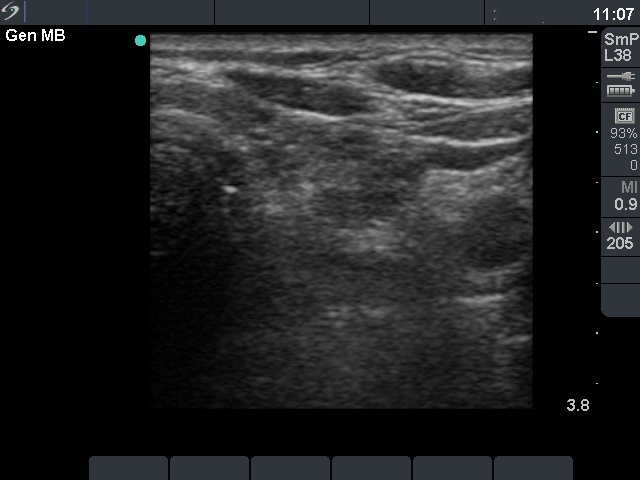

Ethanol sclerotherapy: parathyroid lesions - Case 2

Six months after the therapy (ultrasonographic picture 1)

Under the left lobe. A dramatic shrinkage of the nodule is demonstrated.